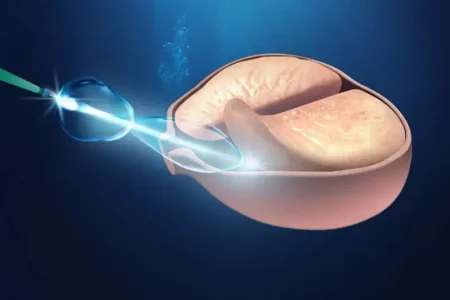

Uma característica notável do câncer de próstata , mesmo em sua fase inicial e restrito à glândula, é sua natureza multifocal. Isso significa que múltiplos focos tumorais podem coexistir dentro da mesma próstata, o que representa um desafio significativo para a eficácia de terapias focais, como o HIFU (Ultrassom Focalizado de Alta Intensidade), ou ressecções parciais. Por essa razão, os tratamentos locais mais estabelecidos e eficientes para curar o câncer de próstata localizado geralmente envolvem a abordagem de toda a glândula. Para os casos de câncer de próstata avançado ou metastático, são necessárias combinações de tratamentos sistêmicos, os quais se mostram muito eficazes no controle da doença e na melhoria da qualidade de vida do paciente.

- Outras (HIFU, Crioterapia): Para casos selecionados, como recidivas locais.